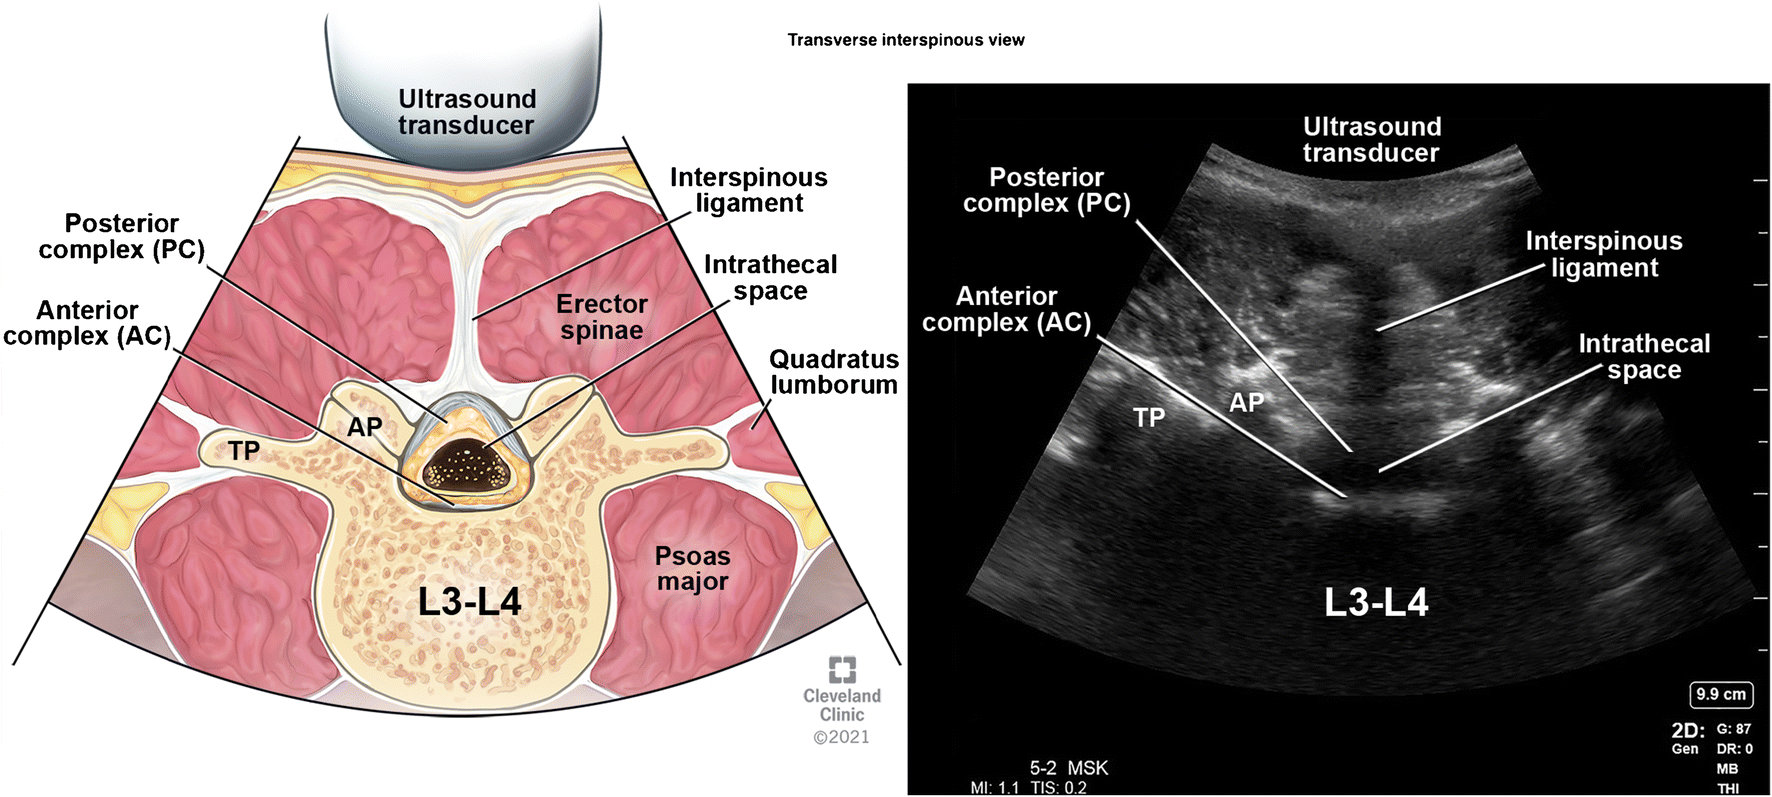

Поперечный межостистый вид

После идентификации остистого отростка датчик перемещают краниально или каудально в межостистое пространство (рис. 5, положение зонда B).

Этот вид, также известный как поперечный интерламинарный вид, позволяет визуализировать задний и передний комплексы вместе с суставными и поперечными отростками латерально (рис. 15).

В этой проекции можно отметить глубину заднего комплекса от кожи, что полезно для определения эпидуральной анестезии.

Угол датчика, необходимый для визуализации заднего и переднего комплексов в этой проекции, облегчает угол падения для введения иглы для успешного нейроаксиального размещения.

После идентификации заднего и переднего комплексов чернильные метки делаются в горизонтальном и вертикальном направлениях и соединяются вместе, чтобы отметить точку входа для нейроаксиальных процедур (рис. 17 и 18).

Внутриоболочечное пространство рассматривается как гипоэхогенное пространство между задним и передним комплексами.

Беспрепятственное межламинарное пространство — это пространство, в котором можно четко визуализировать как задний, так и передний комплексы.

Для доступа к нейракси можно использовать самое широкое беспрепятственное пространство. Это делается путем перемещения ультразвукового датчика в каудальном и краниальном направлениях в поперечном межостистом отростке.

Сохранение видимости переднего комплекса на большем расстоянии указывает на более широкое межостистое пространство.

Рис. Поперечный межостистый вид.